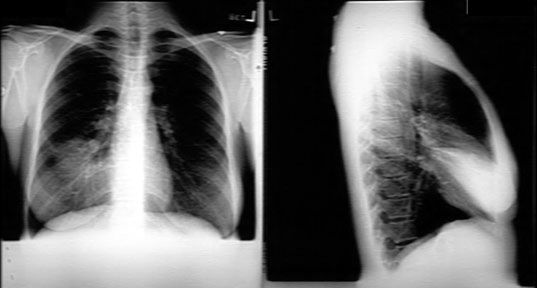

RML Consolidation

-

Radio opaque density in the projection of right lower lung field.

The right diaphragm is clearly seen, excluding lower lobe disease.

The right heart margin is indistinct, indicating right middle lobe disease (silhouette sign).

In the lateral chest x-ray you see a triangular density narrow at hilum and broad towards the chest wall corresponding to RML.

The transverse fissure and oblique fissures are in their normal location. No loss of RML lung volume.

There is air bronchogram, but it is not seen clearly in this presentation.